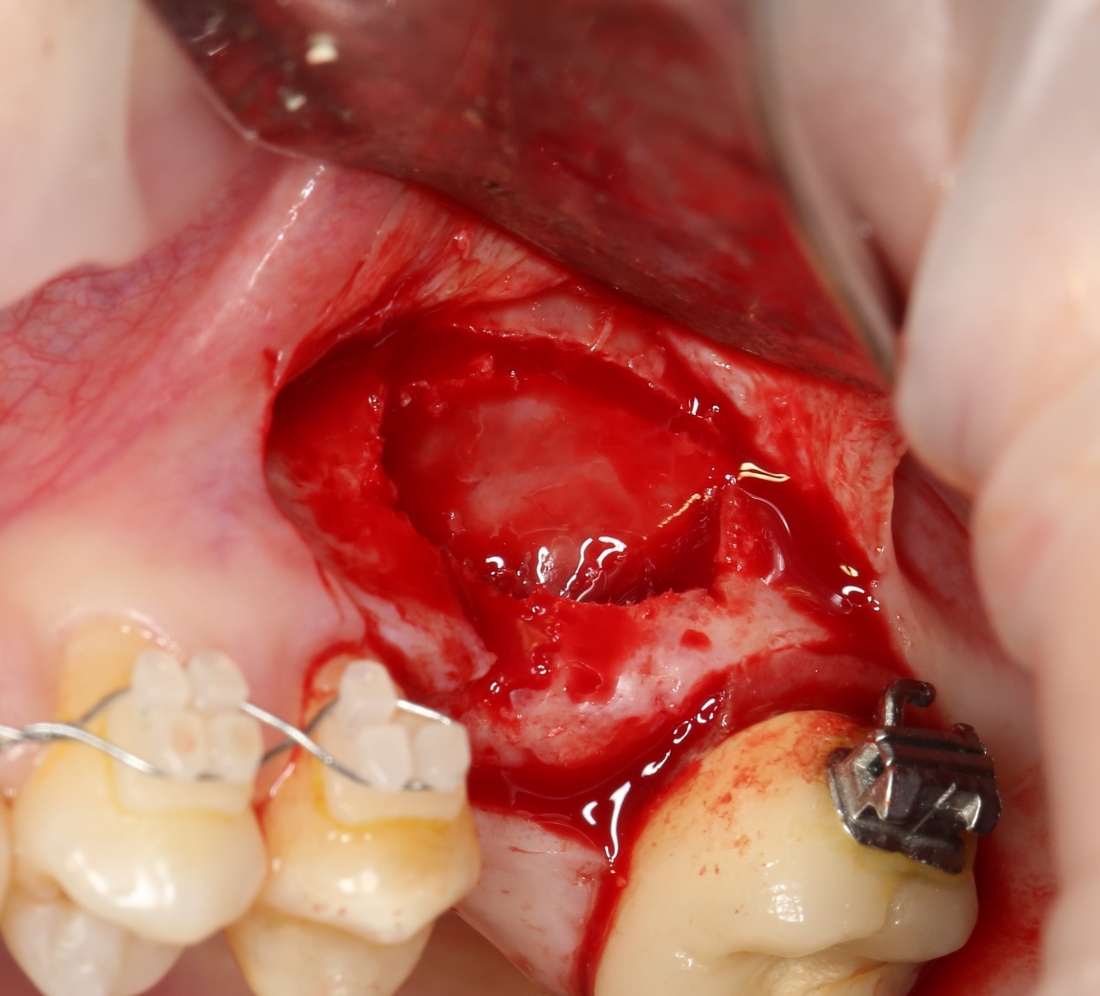

Синуслифтинг: что делать при перфорации слизистой оболочки гайморовой пазухи?